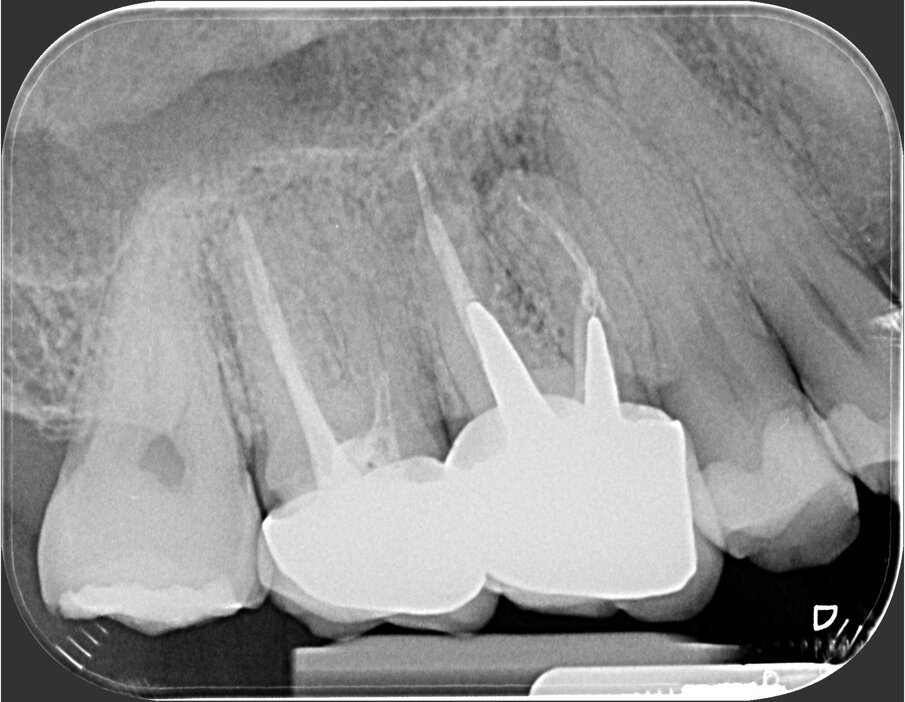

Fig. 2c - La CBCT mostra l’inclinazione distale della radice distovestibolare del primo molare.

Fig. 2d - La sezione coronale mette in evidenza il fatto che la radice distovestibolare del primo molare è vestibolare alla radice mesiovestibolare del secondo molare.

Fig. 2e - Le quattro sezioni assiali mostrano come la radice distovestibolare del primo molare sia vestibolare rispetto alla radice mesiovestibolare del secondo molare. Questa particolare situazione anatomica rappresenta una ovvia controindicazione all’approccio chirurgico.